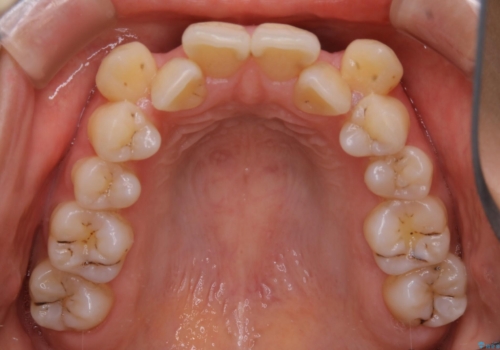

- 以前からコンプレックスだった八重歯の治療を主訴にご来院されました。

検査の結果、抜歯をすることでスペースを作って並べる方法が選択され、ワイヤー装置を用いた治療を開始することとなりました。

奥歯の上下のズレ等は軽度で、必要なスペースと抜歯により作られるスペースがほぼ等量だったため治療の単純化が計れ、大きな移動・見た目の劇的な変化に対して比較的早期での治療完了となりました。

叢生の度合いが重く、抜歯が必要なケース。八重歯の部分以外には大きな問題は認められなかったため、劇的変化が起こる治療でも比較的短期間で終了することができました。